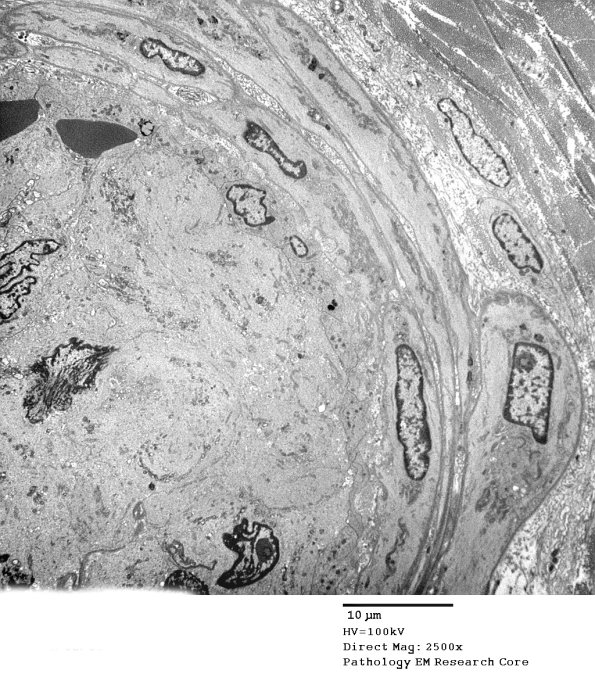

The thrombus shown in 11C6,7 is shown in a low magnification electron micrograph. (electron micrograph)